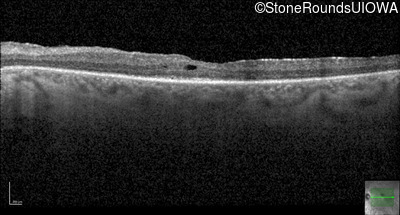

Age at visit:

29 years

OD

OS

20/25 -2

AR Retinitis Pigmentosa

ZNF408

His455Tyr CAT>TAT

Arg567Stop CGA>TGA

AR